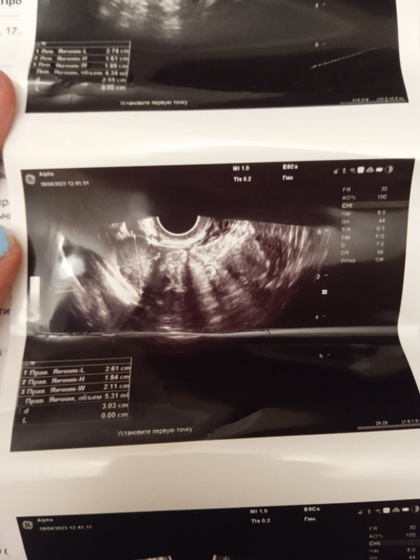

Девушки здравствуйте скажите пожалуйста что это такое задержка 18-19 дней. муж с сво на две недели приехал, последние месячные были 10 марта. Поехала на УЗИ сдала хгч в альфе но внятного ни чего не сказали единственное сказали жёлтое пятно и все. Я просто не понимаю. Объясните пожалуйста

Ну так хгч можно сказать нулевой, тут даже думать не чего…тест показал что?

По хгч, беременности нет.